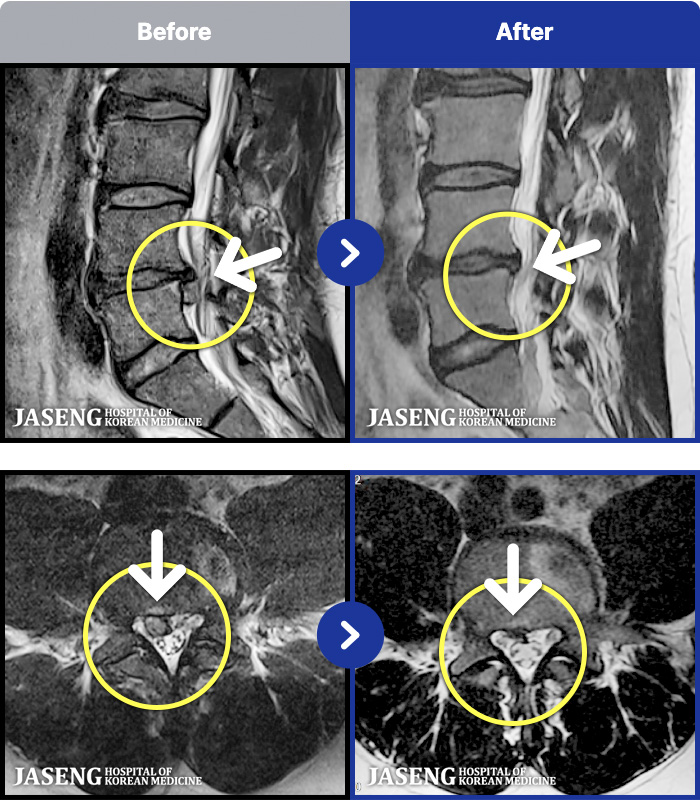

54 MRI ũ ʸ Ȯϼ.